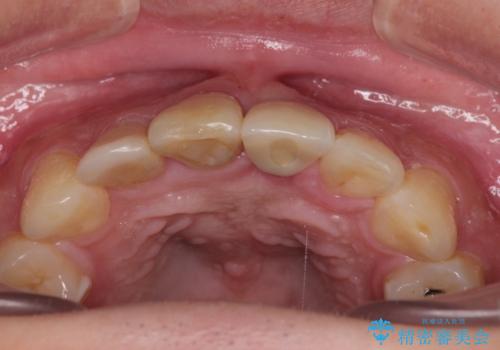

日中は仮歯の着いた床タイプのリテーナーを装着していていましたが、仮歯が装着された段階でマウスピースタイプのリテーナーに変更しました。